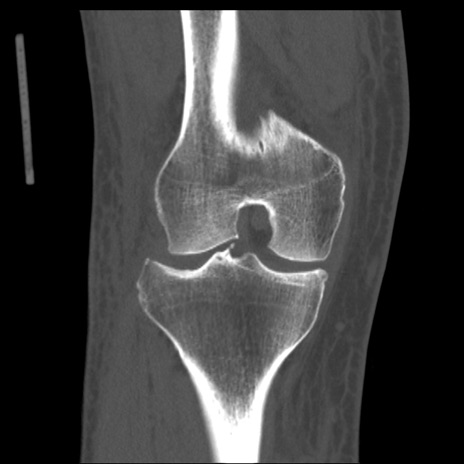

症例28 右膝関節CT(冠状断像)

右膝関節CT